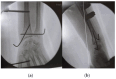

Distal radioulnar joint (DRUJ) instability is a complex condition that can severely affect forearm function, causing pain, limited range of motion, and reduced strength. This review aims to consolidate current knowledge on the diagnosis and management of DRUJ instability, emphasizing a new classification system that we propose. The review synthesizes anatomical and biomechanical factors essential for DRUJ stability, focusing on the interrelationship between the bones and surrounding soft tissues. Our methodology involved a thorough examination of recent studies, incorporating clinical assessments and advanced imaging techniques such as MRI, ultrasound, and dynamic CT. This approach allowed us to develop a classification system that categorizes DRUJ injuries into three distinct grades. This system is intended to be practical for both clinical and radiological evaluations, offering clear guidance for treatment based on injury severity. The review discusses a range of treatment options, from conservative measures like splinting and physiotherapy to surgical procedures, including arthroscopy and DRUJ arthroplasty. The proposed classification system enhances the accuracy of diagnosis and supports more effective decision making in clinical practice. In summary, our findings suggest that the integration of advanced imaging techniques with minimally invasive surgical interventions can lead to better outcomes for patients. This review serves as a valuable resource for clinicians, providing a structured approach to managing DRUJ instability and improving patient care through the implementation of our new classification system.